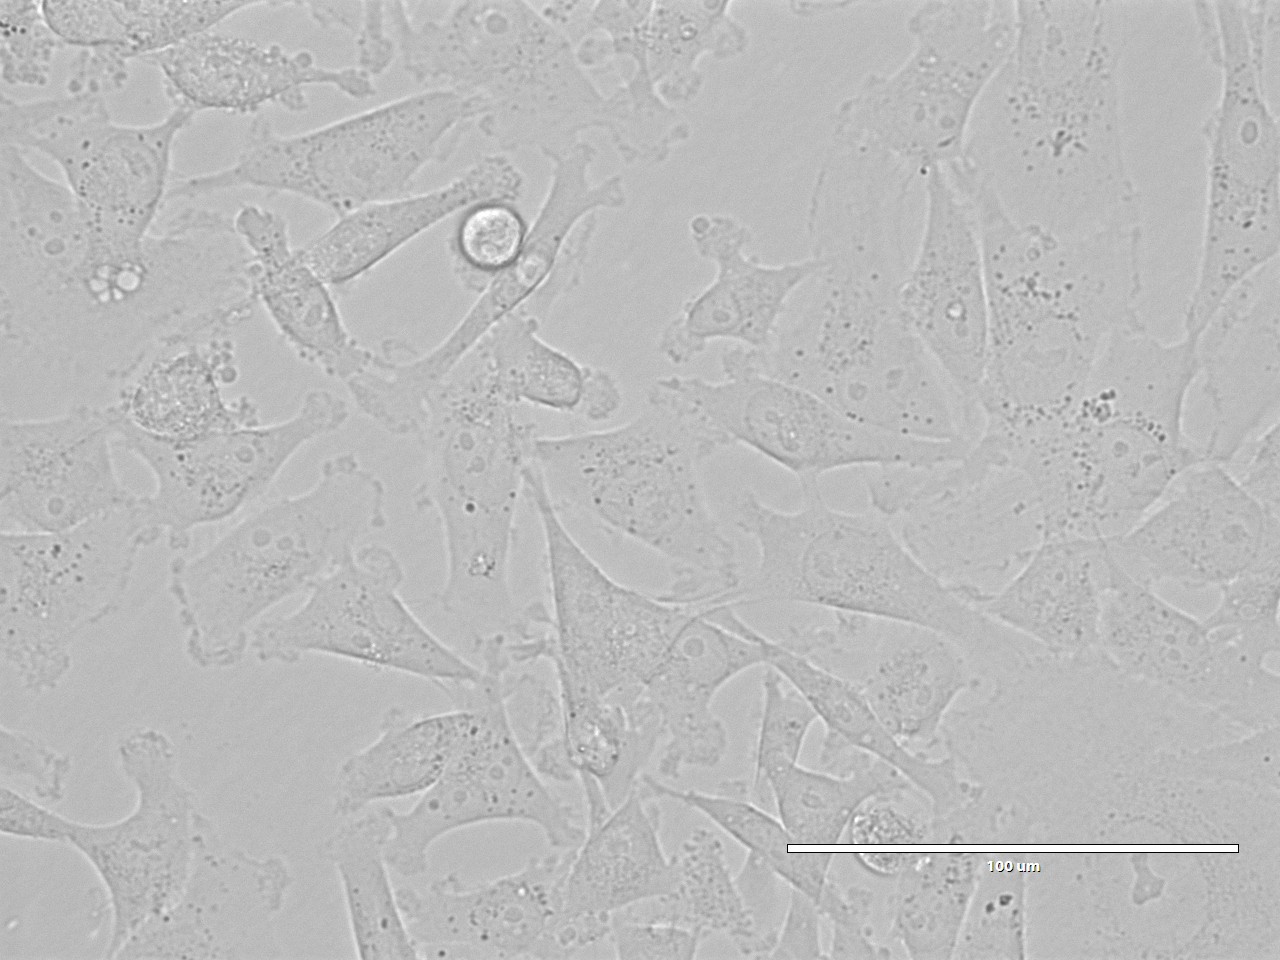

MDA-MB-231(人乳腺癌细胞)

MDA-MB-231(人乳腺癌细胞)MDA-MB-231是从一名51岁的白人女性乳腺癌患者的胸水中分离建立的。该细胞表达表皮生长因子EGF受体、TGF-α受体和WNT7B癌基因。常用于肿瘤转移和侵袭性的研究。

细胞形态 上皮细胞样

生长特性 贴壁细胞